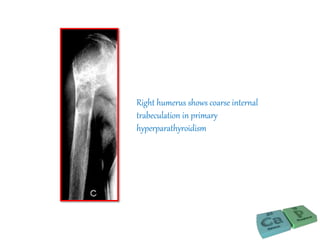

Right humerus shows coarse internal

trabeculation in primary

hyperparathyroidism